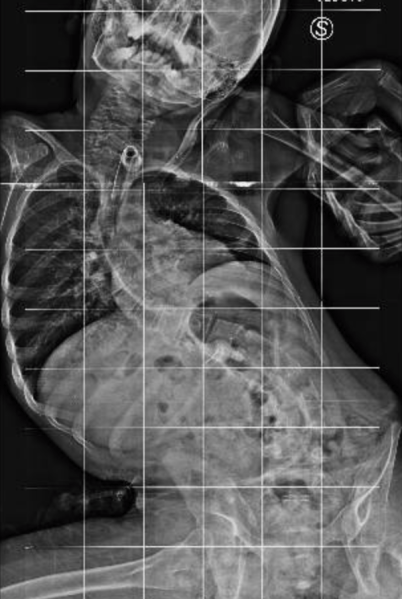

Qui di seguito, un esempio di un paziente affetto da scoliosi severissima, sottoposto a trattamento chirurgico.

Prima dell’intervento:

Schermata 2018-10-07 alle 22.31.01    Schermata 2018-10-07 alle 22.31.16

Dopo l’intervento:

Schermata 2018-10-07 alle 22.30.15     Schermata 2018-10-07 alle 22.30.39